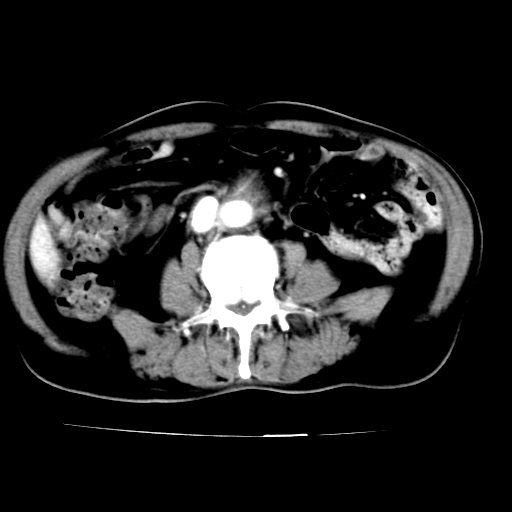

作者: sunhua666    时间: 2007-5-25 03:22

此病例平扫图像已发,请大家看看!